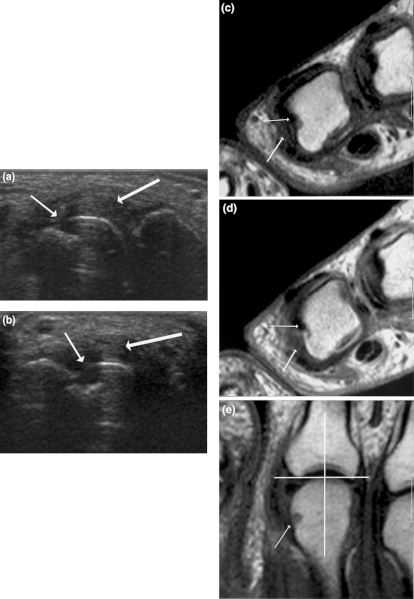

- Thoracic Ultrasound – this test is superior to any other tests in determining the respiratory conditions.